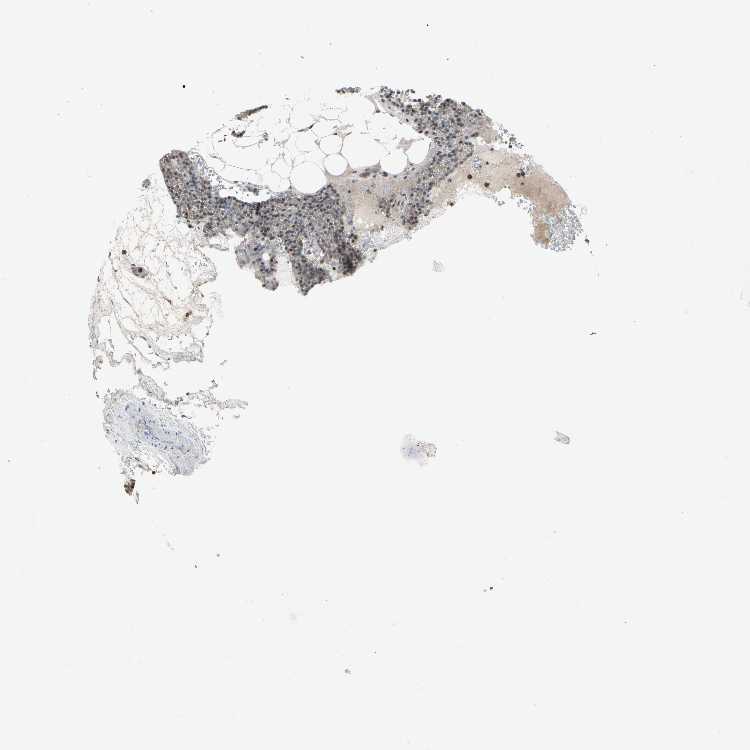

TISSUE PRIMARY DATA PARATHYROID GLAND Show tissue menu

PARATHYROID GLAND - Antibody stainingi

Antibody staining in the annotated cell types in the current human tissue is reported as not detected, low, medium, or high, based on conventional immunohistochemistry profiling in selected tissues. This score is based on the combination of the staining intensity and fraction of stained cells.

Each image is clickable and will lead to virtual microscopy that enables deeper exploration of all samples and also displays staining intensity scores, fraction scores and subcellular localization as well as patient and tissue information for each sample.

Antibody HPA035832Antibody CAB011442Antibody CAB079996Antibody CAB080305

Glandular cells Not detectedLowNot detectedHigh